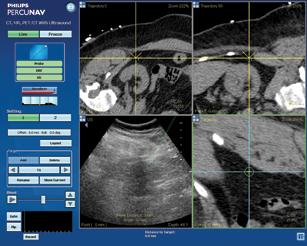

Figure 2: The Navigator DS is set up, with the image-guided needle placing medication into the ankle joint.

The Yale University School of Medicine has implemented the Navigator DS delivery system, a computer-controlled, image-guided injection system intended to increase the accuracy, efficiency and safety of musculoskeletal injections.

The Navigator DS prepares physician-prescribed injections from standard multi-dose anesthetic and steroid drug vials, while the ultrasound screen provides the physician with real-time visualization of the needle position, fluid delivery process and prescription volume. This is important, as accurate drug delivery may help to reduce the need for repeat injections, which in turn reduces costs and improves patient care. Precise dose preparation also helps to ensure that doctors use no more or less drugs than needed.

By simplifying the injection set-up process and utilizing ultrasound guidance, preparation time is reduced to just minutes and the procedure can be performed by a single operator. After the injection is delivered to the painful joint, the system records the treatment data and automates a record for transfer to an electronic record management system or direct printout. Initial studies demonstrate that a moderately busy practice can save more than 30 minutes in preparation time in a typical day.

As can be see on his X-rays (Figure 1, below), there was significant joint destruction in both the ankle (tibiotalar) and subtalar joints. Sequential targeted injection into first the ankle joint, followed (if needed) into the subtalar joint, would allow Mr. RS to “test-drive” any further intervention on these related, but separate, joints. Figure 2, above, shows the Navigator DS setup with the image-guided needle placing medication into the ankle joint. The procedure was completed in less than two minutes.